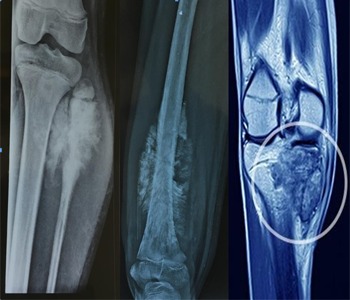

Q. How is the diagnosis made?

For soft tissue sarcomas to be effectively managed, an accurate diagnosis is essential. The doctor can advise a biopsy to take a sample of tissue from the tumor for analysis in a lab. Recurrence risk is decreased and the likelihood of a proper diagnosis and course of therapy is increased when evaluation takes place in a cancer center with a large patient base for sarcoma and a dedicated sarcoma management team.